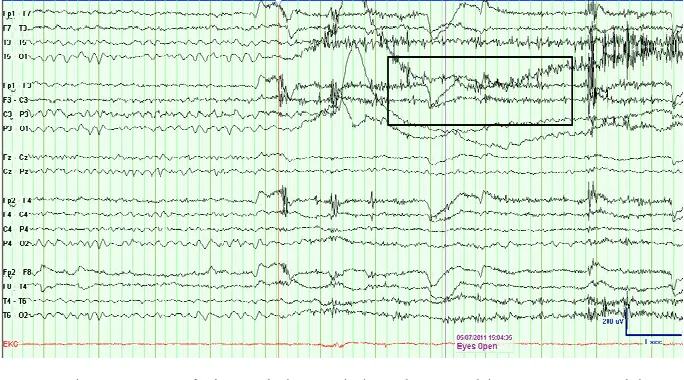

要了解医生在比较脑癌患者和健康人的神经活动时会注意什么,请看这些图片。

下图是脑癌患者的脑电图读数示例。

在一名 46 岁胶质瘤患者的脑电图中观察到缓慢的阿尔法活动。高亮区域显示阿尔法节律紊乱。